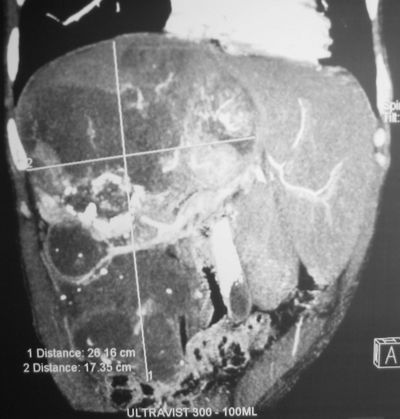

КТ органов брюшнйо полости